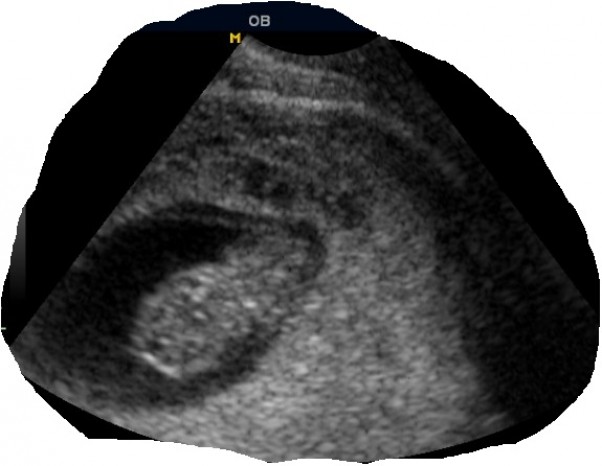

9 tygodni :)

Byłam na kolejnej wizycie dzisiaj i mogłam zobaczyć jak bardzo się zmieniło moje dziecko przez 4 tygodnie-od czarnej plamki po zarys całego ciałka rączek nóżek małej główki i bijącego serduszka :D ogromne zmiany zaszły wewnątrz mnie a na zewnątrz prawie nie widoczne ;) wycięłam zdjęcie usg i noszę go przy sobie w portfelu <3